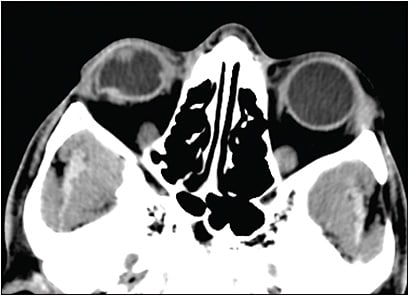

Diagnosing retained IOFBs can be challenging, especially if they are small and nonmetallic. Ocular imaging using CT scan (axial 1-mm cuts with sagittal and coronal reconstruction images) should be performed in all suspicious cases (Figures 2 and 3). Identification of the IOFB depends on the radiodensity of the material.44 Helical CT scanners have a resolution of 0.6 mm,45,46 but small plastic, glass, or wood pieces (<0.5 mm) can be missed, especially if there is extensive VH and the globe is disorganized due to injury (Figure 4). Such cases may require further investigation using MRI,47,48 provided that the IOFB is not magnetic. Newer ocular ultrasonography machines are very sensitive and may detect extremely small radiolucent materials. Use of echography in the setting of an open-globe injury requires an experienced echographer, because undue pressure on the globe can exacerbate the extent of injury and increase the risk of infection.